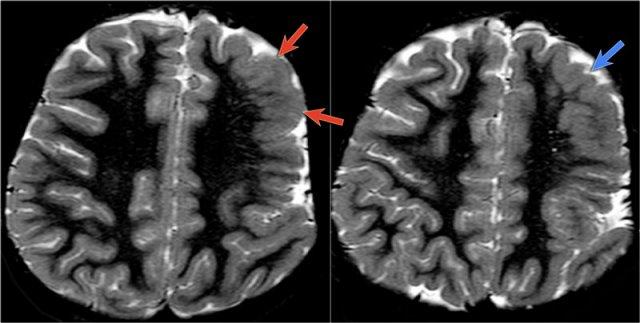

Các hình ảnh cho thấy loạn sản vỏ não khu trú điển hình.

Có hình ảnh dày vỏ não và mờ ranh giới chất xám/chất trắng trên chuỗi xung T1W (bên trái).

Ảnh FLAIR bên phải cho thấy tăng tín hiệu vùng dưới vỏ.

Các hình ảnh cho thấy bất thường tín hiệu vỏ não và dưới vỏ trên chuỗi xung T2W và FLAIR ở thùy thái dương trái, phù hợp với loạn sản vỏ não khu trú.

Lưu ý hình ảnh hồi hải mã tăng tín hiệu T2/FLAIR kèm teo nhỏ là hậu quả của xơ cứng thùy thái dương giữa, tức là bệnh lý kép.